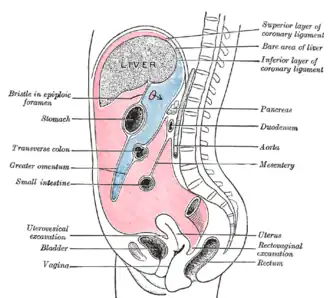

Peritoneal folds are omentums, mesenteries and ligaments; they connect organs to each other or to the abdominal wall.[4] There are two main regions of the peritoneal cavity, connected by the omental foramen.

- The greater sac, represented in red in the diagrams above.

- The lesser sac, represented in blue. The lesser sac is divided into two "omenta":

- The lesser omentum (or hepatogastric) is attached to the lesser curvature of the stomach and the liver.[5]

- The greater omentum (or gastrocolic) hangs from the greater curvature of the stomach and loops down in front of the intestines before curving back upwards to attach to the transverse colon.[5] In effect it is draped in front of the intestines like an apron and may serve as an insulating or protective layer.[5]

In addition, in the pelvic cavity there are several structures that are usually named not for the peritoneum, but for the areas defined by the peritoneal folds:

| Rectouterine pouch | Between rectum and uterus | Female only |

| Vesicouterine pouch | Between urinary bladder and uterus | Female only |